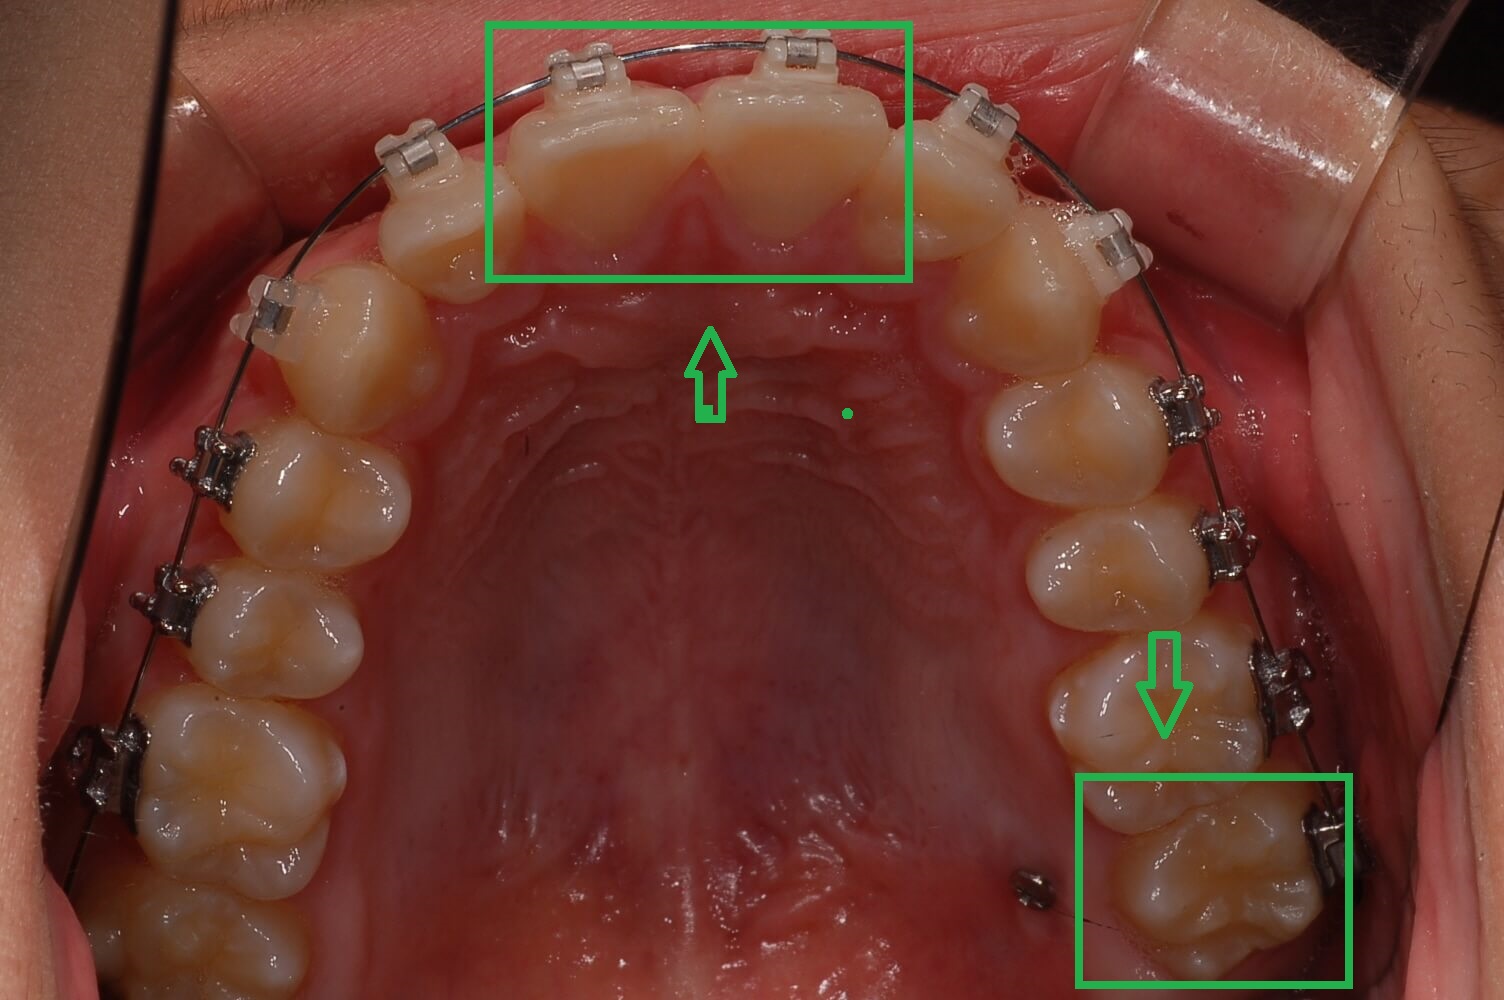

전체 교정 브라켓을 부착 후 2달 정도 지나고 나니 S자로 휘어진 철사가 어느 정도 일자로 복원되면서 앞니의 치아배열이 가지런하게 정리가 되어있습니다.

이제부터 본격적인 장기레이스 정밀하게 교정에 들어가기 위해 2차 정밀 검사를 하게 되는데요. 좀 더 미관적으로 기능적으로 좋은 치료 방향을 잡기 검사를 하였습니다.

교정 진행과정은 순조롭게 진행이 잘되었으며 전체 교정기간 5개월 정도 지난 후 상태를 확인하였고 발치 후 교정, 비발치 교정의 선택만 하면 되었습니다.

위, 아래 발치 2개씩을 하면 치아공간이 생겨 좀 더 나은 교정이 될 수 있지만 비발치를 하여도 크게 문제가 되지 않기에 비발치를 선택하였습니다.

▼ 5개월 교정 후 사진(1)

▼ 5개월 교정후 사진(2)